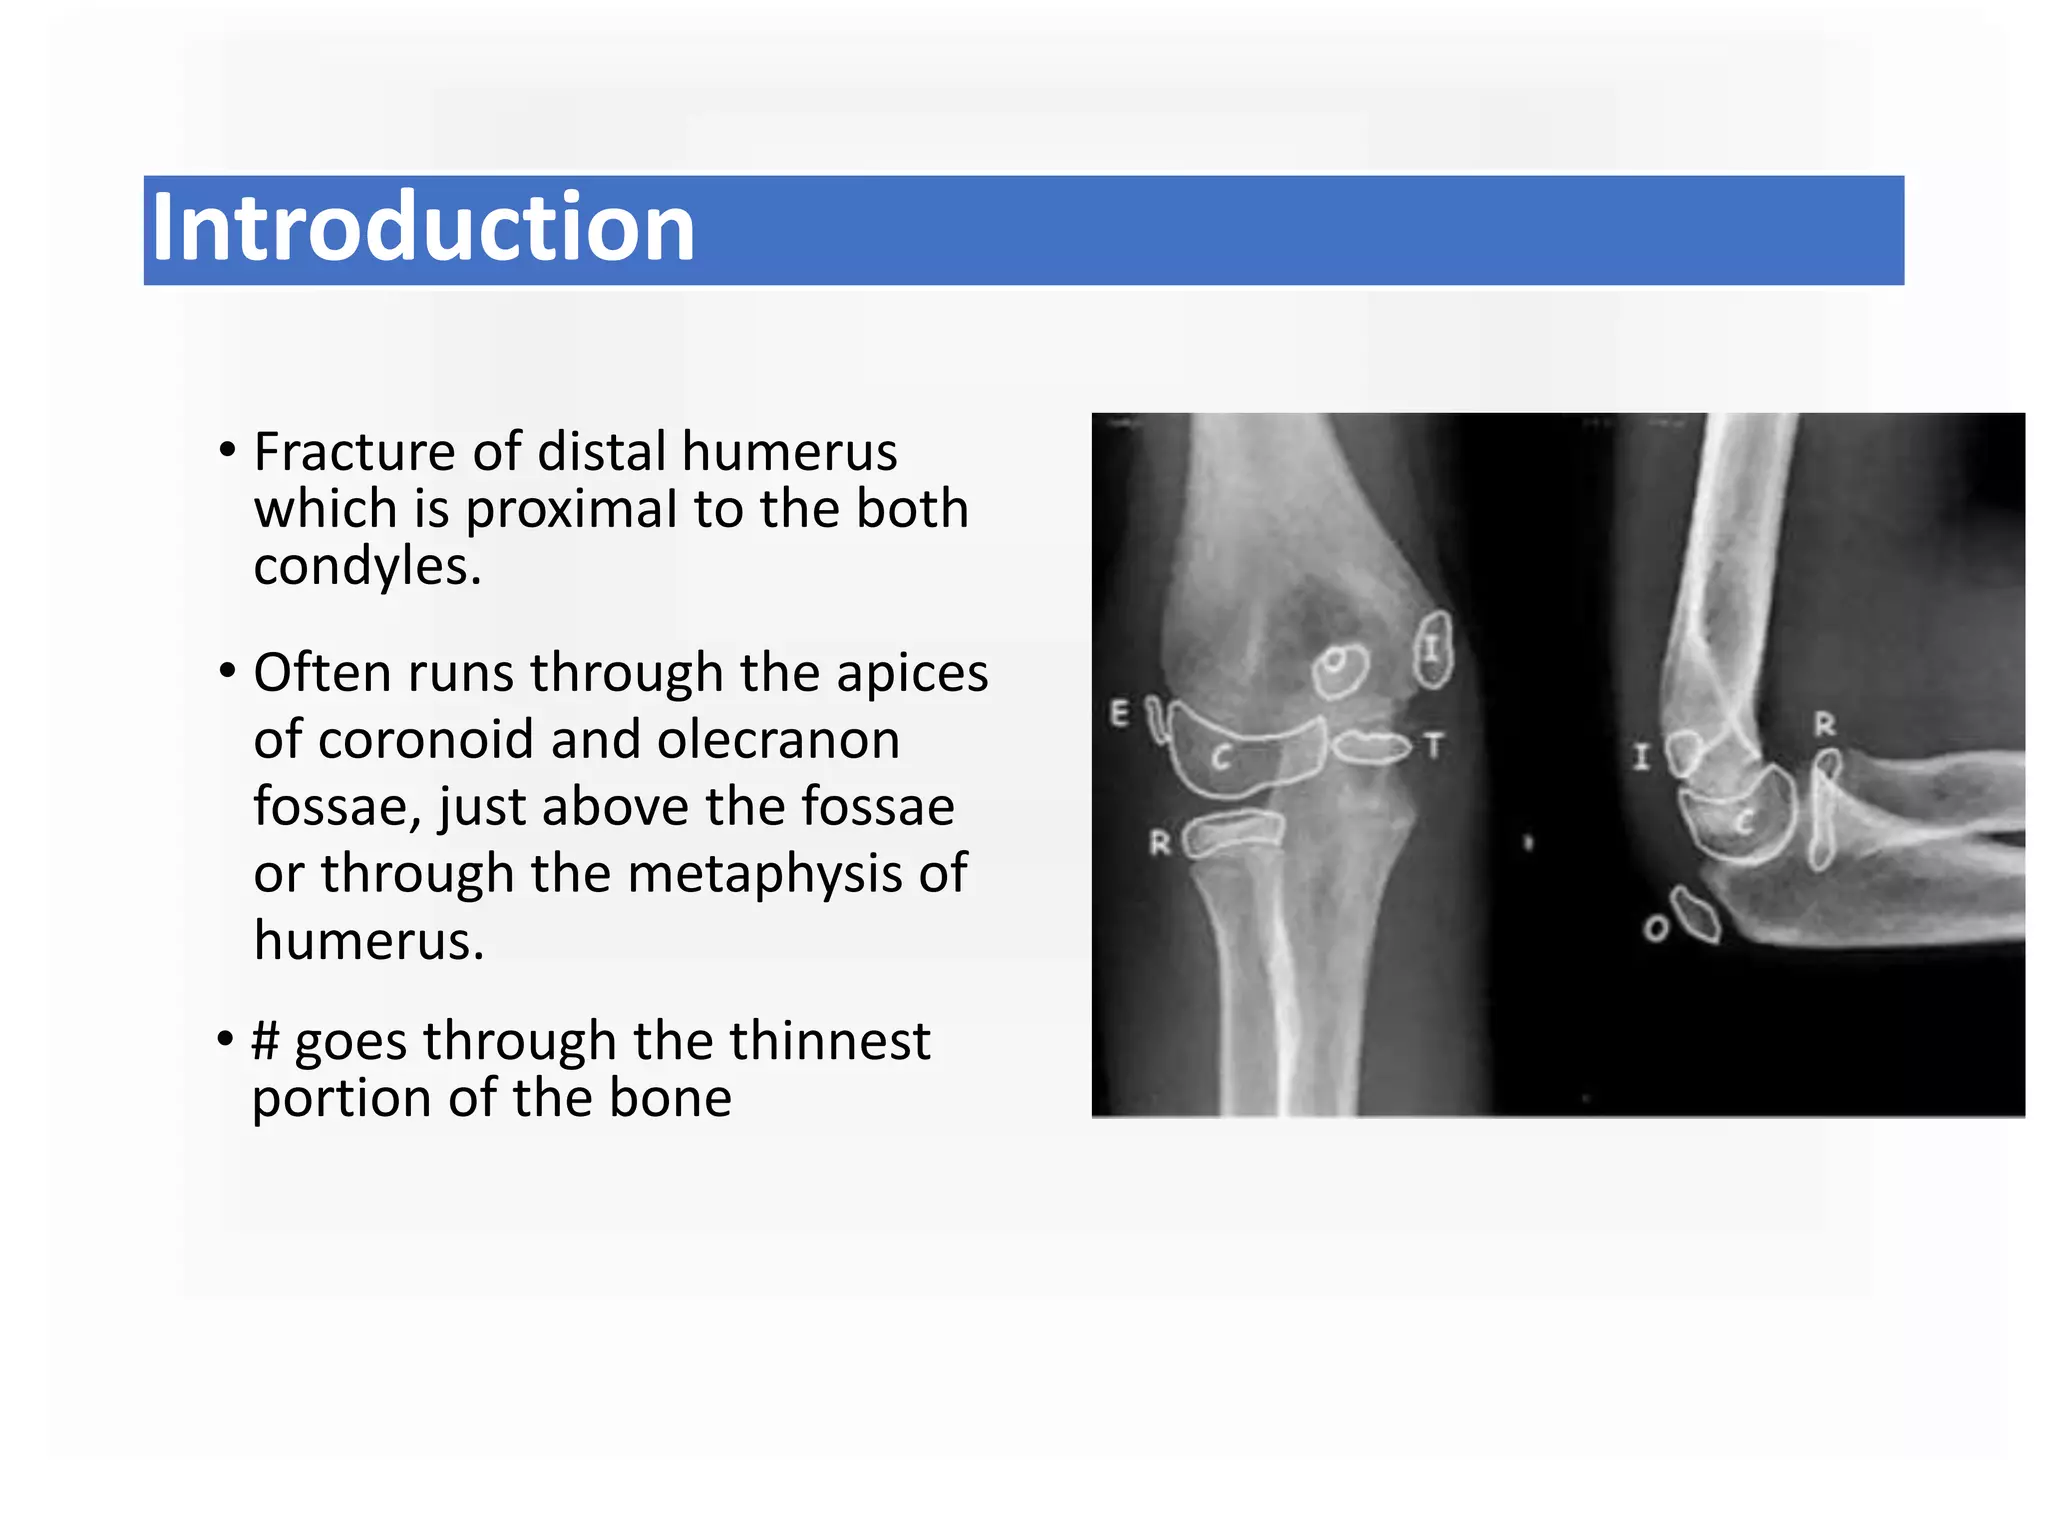

• Fracture of distal humerus

which is proximaI to the both

condyles.

• Often runs through the apices

of coronoid and olecranon

fossae, just above the fossae

or through the metaphysis of

humerus.

• # goes through the thinnest

portion of the bone